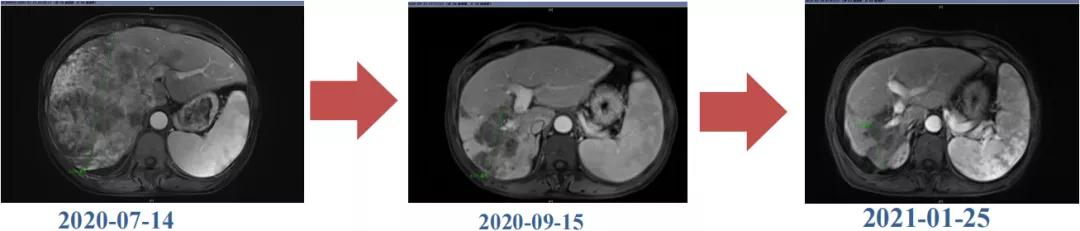

肿瘤学评估(用药后2个月对比6个月):肝内主瘤明显缩小,动脉期强化降低;子灶消失;门脉右支癌栓明显缩小坏死;肺转移灶缩小,大部分消失。

Δ治疗过程中病灶影像学变化

用药6个月后:肝脏病灶明显缩小,子灶消失,仅有少量动脉期强化;肺转移单个持续缩小稳定,PET CT活性弱;HBV DNA 转阴;可考虑转化切除。

术后病理:病理学CR

术后1月复查:磁共振肝内未见肿瘤复发,肺部单个肿瘤稳定。

术后末次随访2021年12月6日,肝内未见明显病灶,肺部病灶稳定1.3cm。

目前OS 17个月,RFS 10个月。